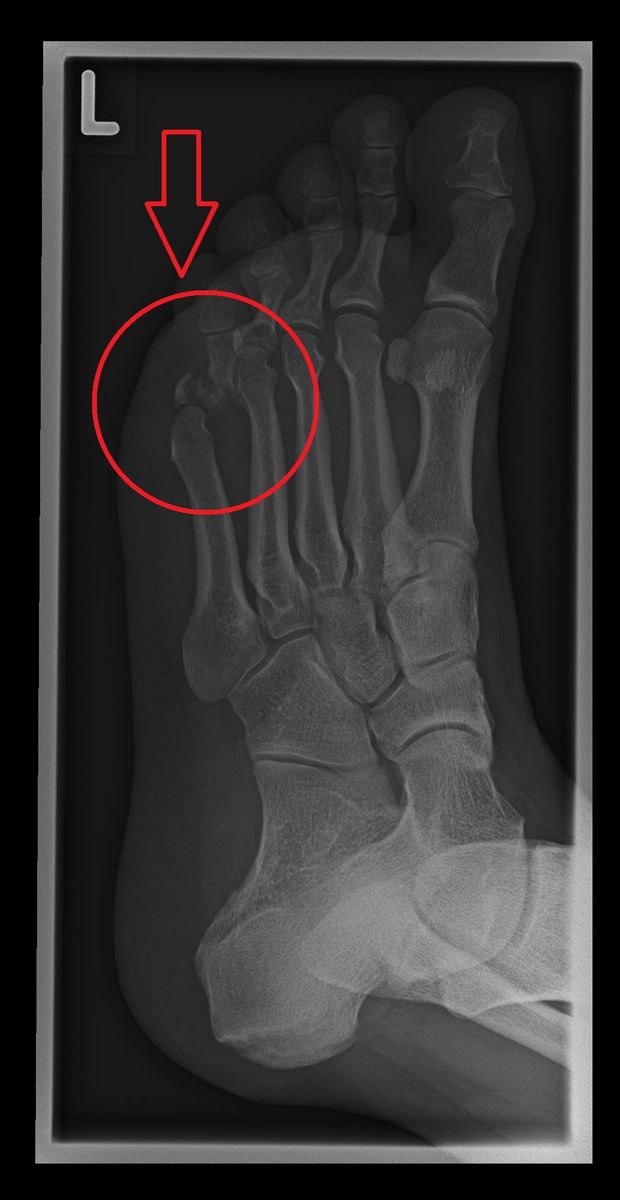

Der gebrochene Zeh infolge des Unfalls

Kommandant Oehrli, sein Fähnrich und vier weiteren Reismusketen läuteten am diesjährigen Zibelemärit mit dem «Ausschiessen» um halb zwölf vor dem Berner Rathaus den Umzug der Zibelegringe zum Kursaal ein. Derweil leiteten Verkehrspolizisten den Verkehr an den Schützen vorbei. Nach der Schussabgabe überwachte Oehrli gerade die Musketen, das korrekte Verstauen des Schiesspulvers und der übrigen Ausrüstung seiner Truppe, dabei erwischte ihn plötzlich bei einem Schritt zur Seite das Hinterrad eines vorbeifahrenden Autos am Fuss. Fuss und Bänder überdehnten sich, unter der Last des Wagens brach der kleine Zeh. Woher das Fahrzeug gekommen war und wieso die Polizisten es übersehen konnten, weiss Oehrli nicht, seine Aufmerksamkeit war ganz auf seine Arbeit als Kommandant gerichtet. Die Aufregung nach dem Unfall war gross, schnell waren Ambulanz und Polizei vor Ort, um den Verletzten zu versorgen und den Hergang zu protokollieren.

Oehrli liess es sich aber nicht nehmen, noch rasch die Übergabe des Kommandos der Schützen zu regeln, schliesslich gehört das zu den Aufgaben eines gewissenhaften Kommandanten. Dann brachte ihn der Krankenwagen ins Spital. Während in der Stadt die Ehrenformation wie geplant den Umzug anführte und mit ihren Salven ein tolles Spektakel für die Zuschauer bot, wurde Oehrlis linker Fuss untersucht und versorgt. Während er im Spital auf die medizinischen Befunde wartete, hielten ihn seine Kollegen per SMS über alles auf dem Laufenden: über geglückte Salven, das Spalierstehen und den gesamten Anlass der Gilde der Zibelegringe der Stadtschützen Bern. Als Oehrli dann die Nachricht erhielt, dass der ehemalige Burgergemeindepräsident Rolf Dähler zum neuen Oberzibelegring gewählt worden war, war er nicht mehr zu halten. Mit dem rasch erteilten Segen seiner Ärzte verliess er das Krankenhaus schnurstracks Richtung Kursaal, um Dähler zur Ehrung zu gratulieren. Diesen freute es, seinen Kommandant wieder auf den Beinen zu sehen. Er verabschiedete ihn später mit den besten Genesungswünschen.